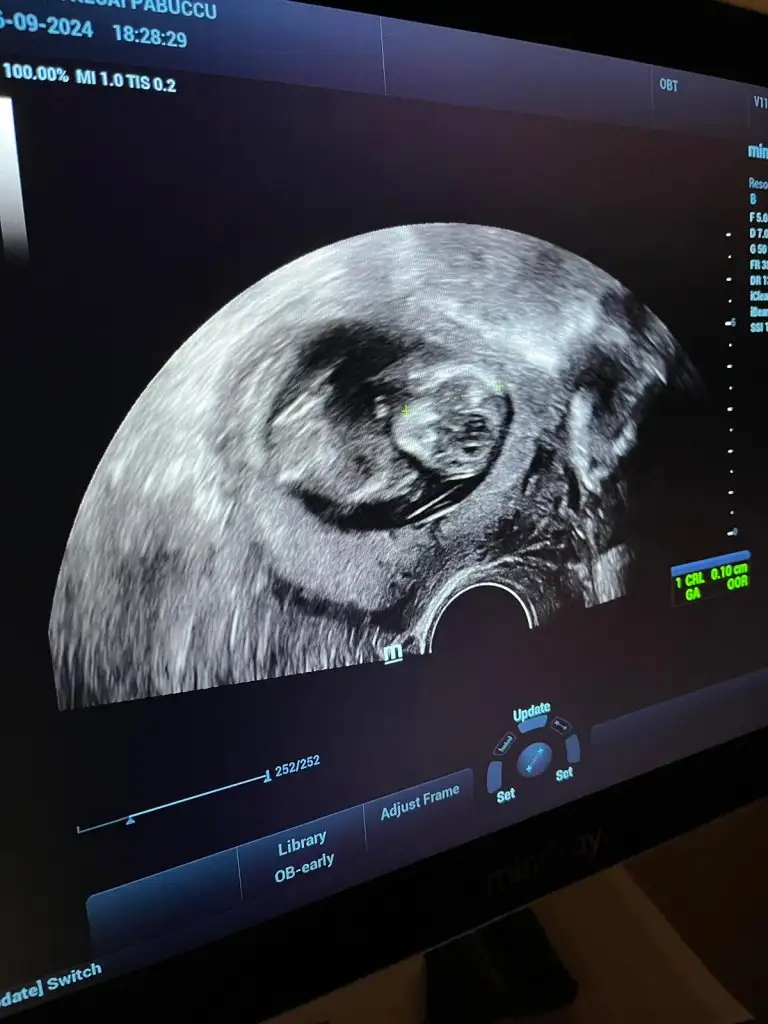

Benimkine de bakar mısınız 12+5 günlük

Bana da tahminde bulunur musunuz 13 haftalık olduk doktor erkeğe benziyor ama 16 haftalıkken belli olur dedi❤️